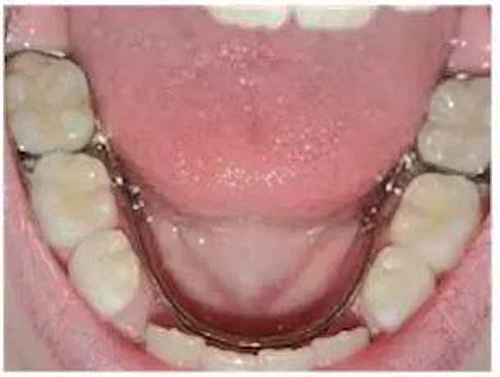

②舌弓式間隙保持器

乳牙缺失致恒牙“亂長”,這個(gè)“間隙保持器”可預(yù)防

這種間隙保持器用于下牙左右兩側(cè)都有缺牙的情況,“舌側(cè)”是指牙齒靠近舌頭的那面。這種保持器的兩端固定在兩側(cè)缺失牙后方的牙齒上,一個(gè)弓絲沿著下牙的內(nèi)側(cè)連接兩段的帶環(huán)。